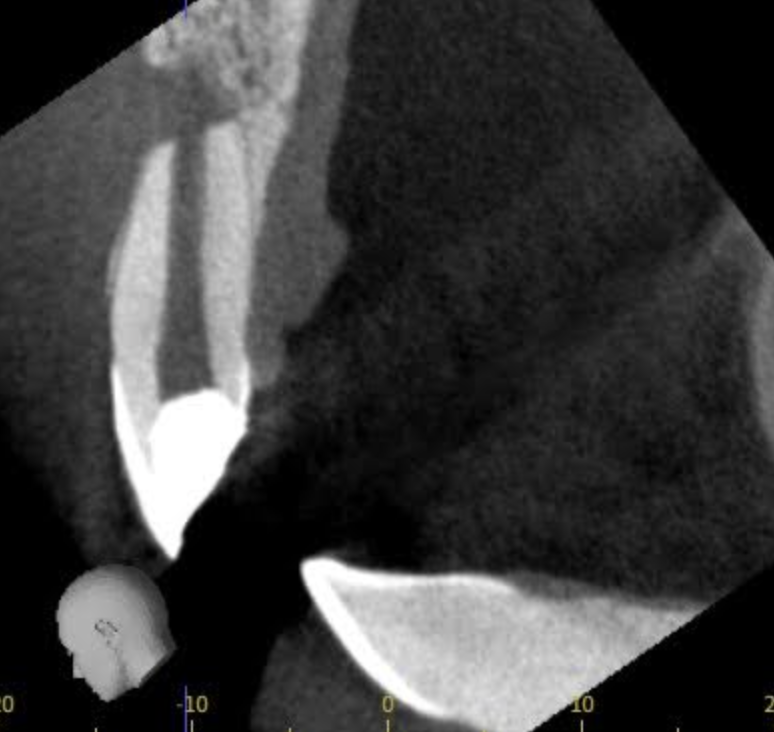

通常の治療では確認できない細かな部分までアプローチするために、CT画像による三次元診断や、マイクロスコープ(歯科用顕微鏡)を使用して処置を進めます。

拡大視野のもとで治療することで、わずかな汚染部位や複雑な根の分岐も見逃さず、再発リスクを大幅に減らすことができます。

こちらが根尖切除術を行なった左上2番(治療前)です。

次の写真は根尖切除術後3ヶ月後で、根尖が順調に治癒し骨が再生してきています。